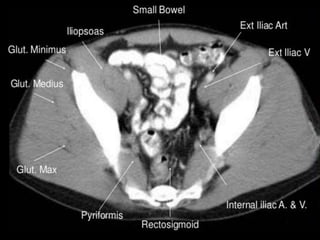

CT cross sectional

anatomy.